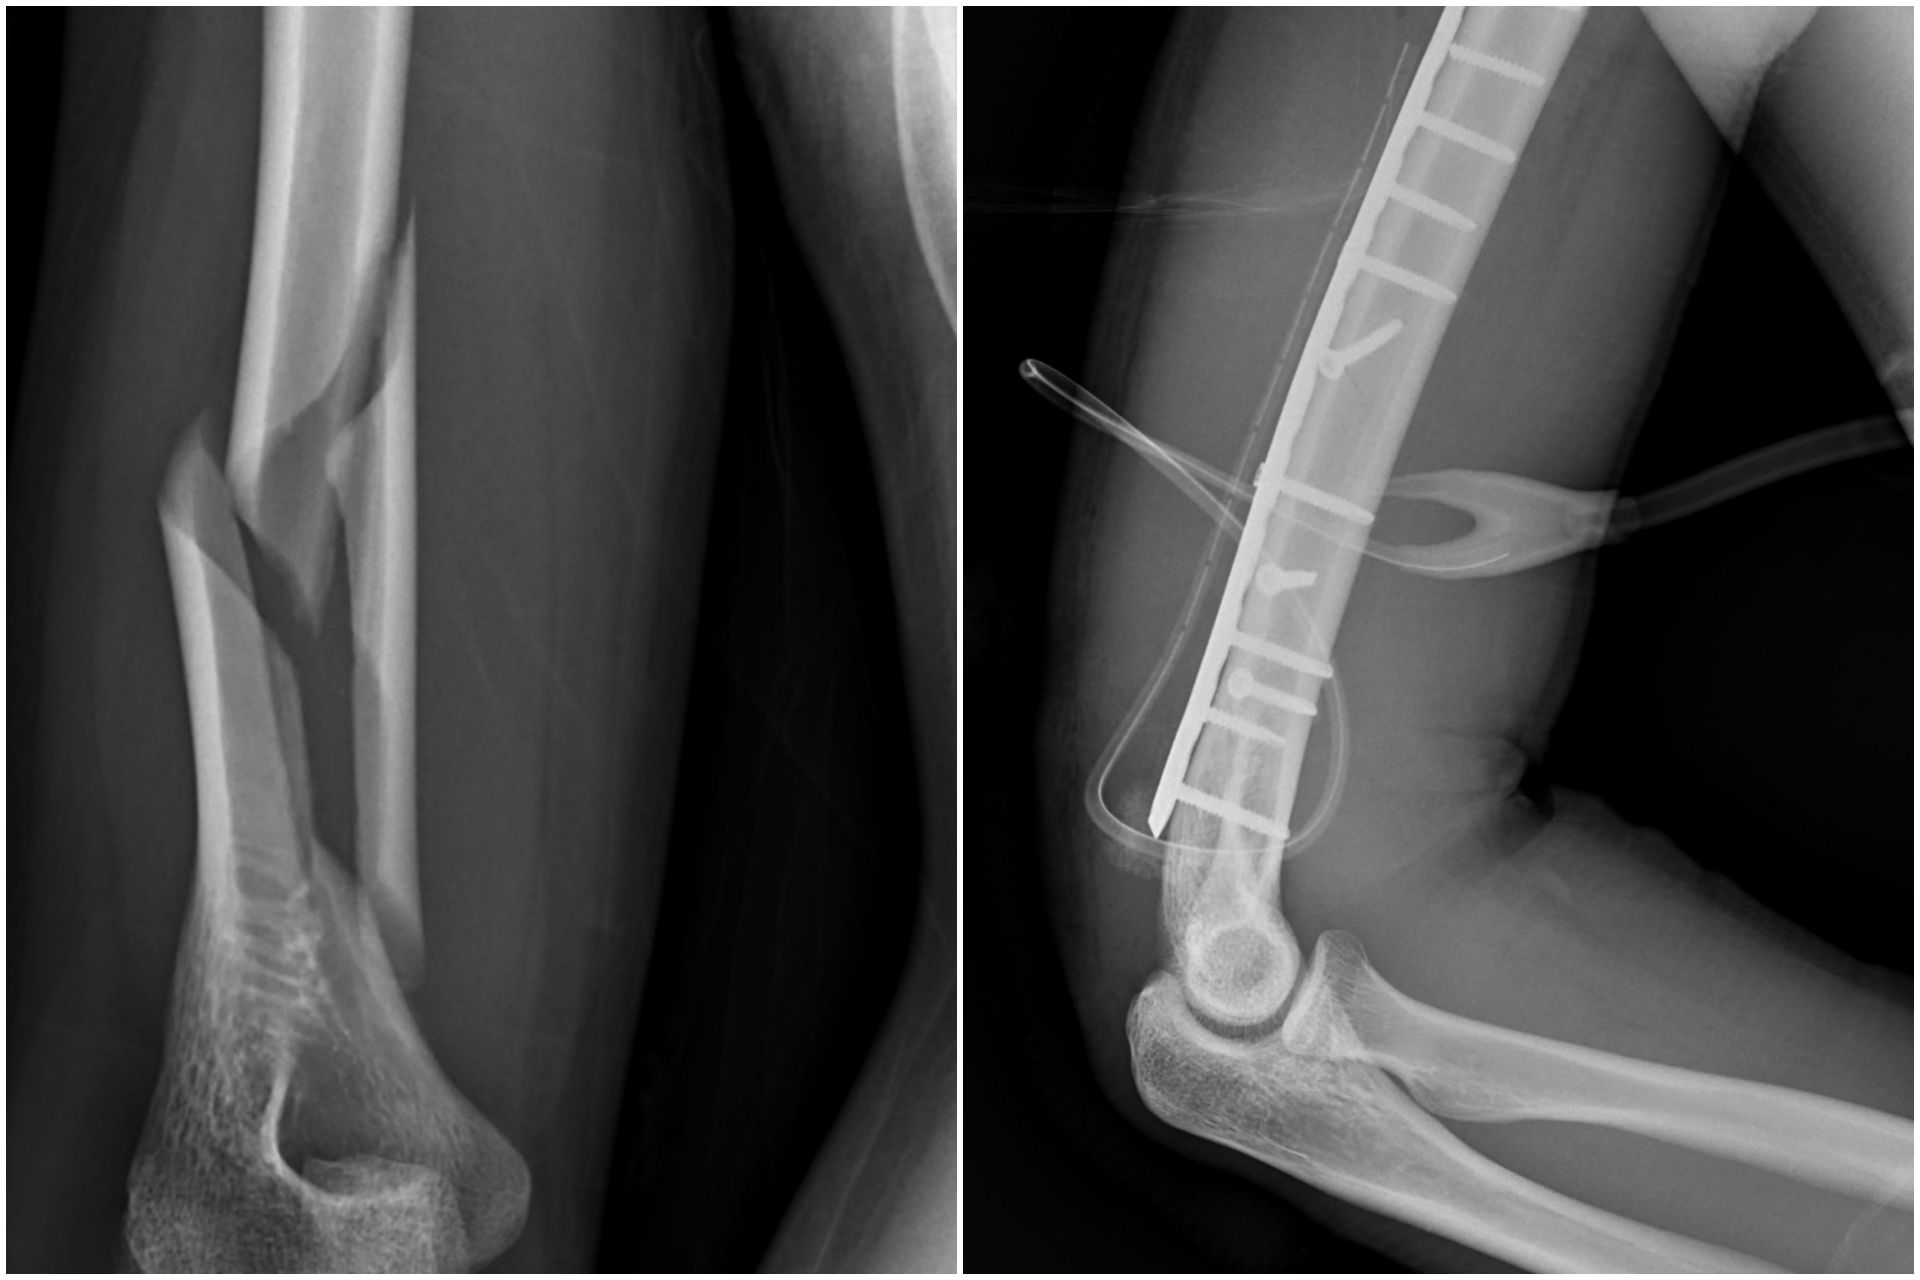

29歲男子與朋友一時興起比腕力,沒想到在激烈對抗下,上臂突然劇痛、當場失去支撐力,就醫檢查為右上臂肱骨螺旋性骨折。花蓮慈濟醫院骨科醫師張家銘指出,比腕力骨折並非罕見,與一般跌倒或撞擊造成的骨折不同,主要來自瞬間強大的扭轉力,提醒民眾切勿逞強,以免樂極生悲。

張家銘醫師說明,腕力比賽時,雙方手臂呈交叉對抗,肩膀會產生內旋動作,前臂如同槓桿,力量集中於肱骨遠端,形成強烈的旋轉扭力,此時若力量超過骨頭強度負荷,便可能造成螺旋性骨折,這種骨折不是外力撞擊,而是因為扭轉造成骨頭就像被擰斷一樣。

治療方面,醫療團隊採取手術方式,自後側切入,在避開神經的前提下進行骨折復位,並以鋼板固定,協助骨頭穩定癒合,經適當治療與復健,多數病人可恢復正常生活與活動能力。